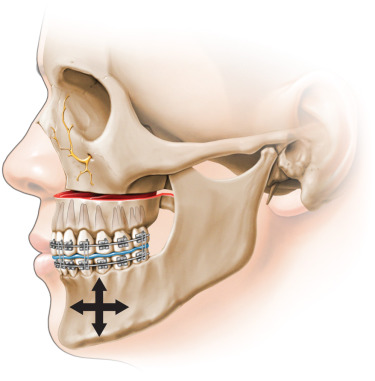

Modified Lefort 1 yes, a standard Lefort will not change anything near ur orbitalsTitle

Get infraorbital rim implants , lefort 1 wont change thatTitle